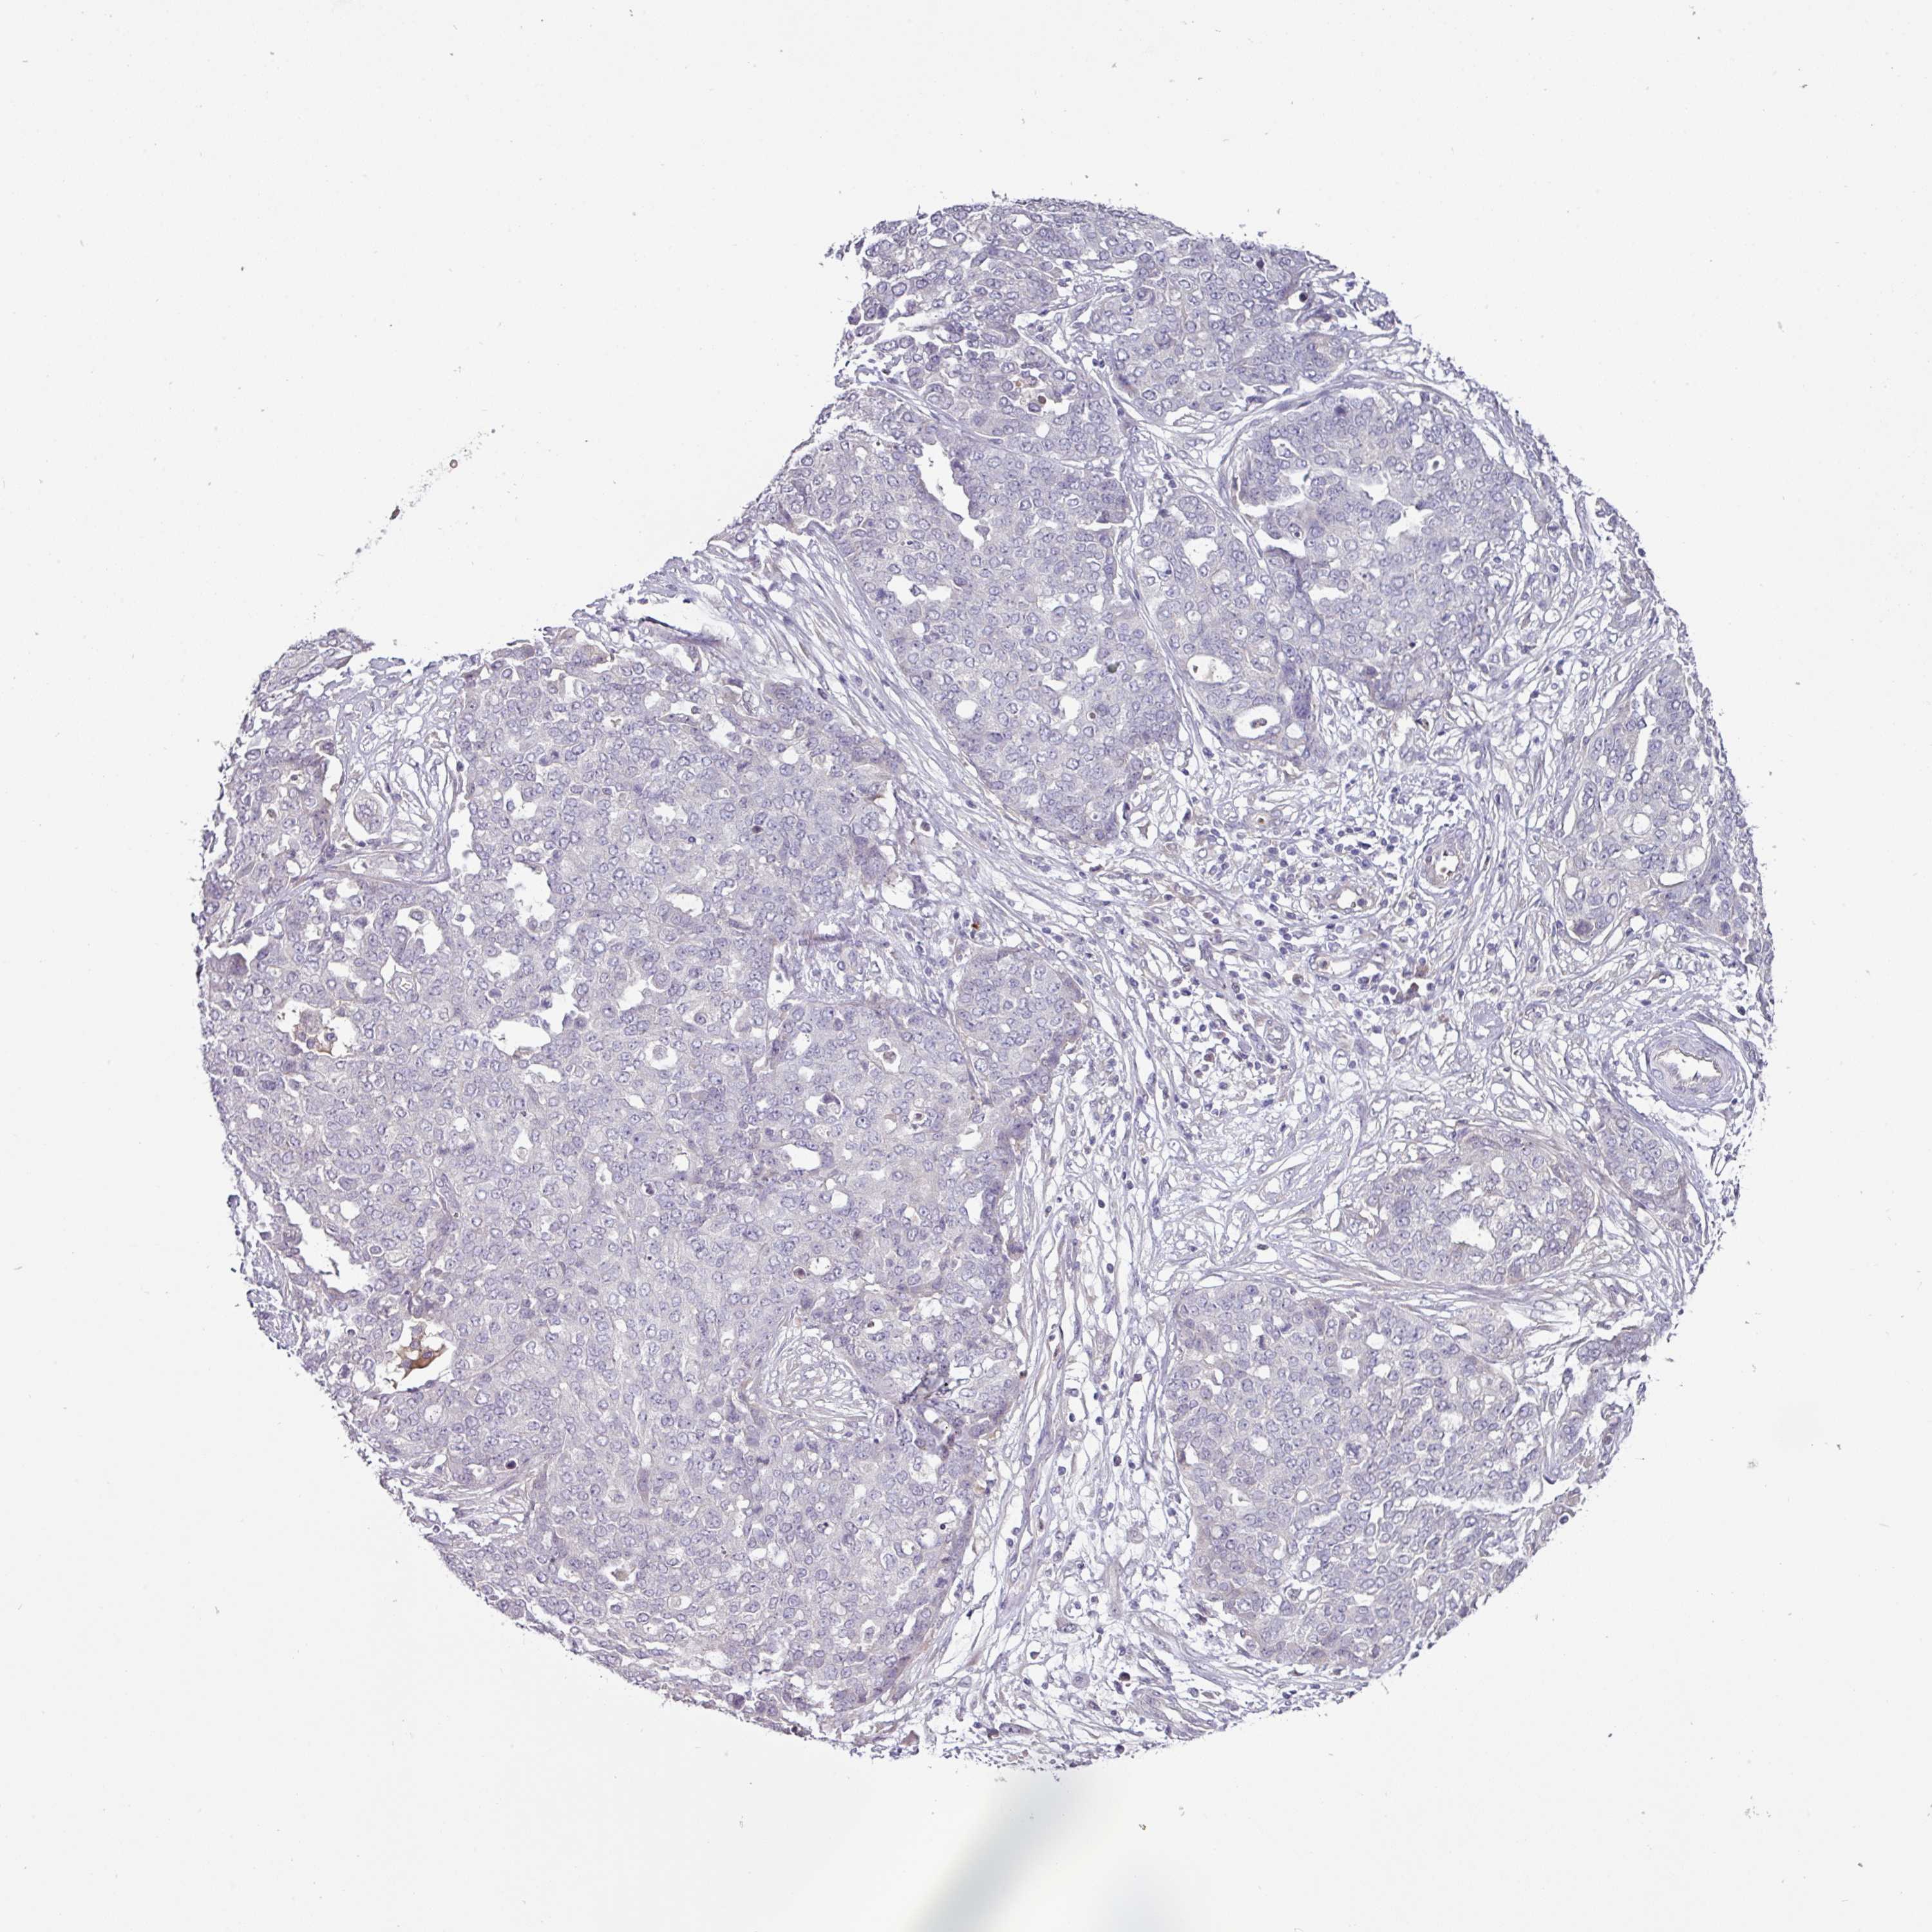

OVARIAN CANCER - Protein expressioni

A mouse-over function shows sample information and annotation data. Click on an image to view it in a full screen mode. Samples can be filtered based on level of antibody staining by selecting one or several of the following categories: high, medium, low and not detected. The assay and annotation is described here.

Note that samples used for immunohistochemistry by the Human Protein Atlas do not correspond to samples in the TCGA dataset.

Antibody stainingi

Antibody staining in the annotated cell types in the current human tissue is reported as not detected, low, medium, or high, based on conventional immunohistochemistry profiling in selected tissues. This score is based on the combination of the staining intensity and fraction of stained cells.

Each image is clickable and will lead to virtual microscopy that enables deeper exploration of all samples and also displays staining intensity scores, fraction scores and subcellular localization as well as patient and tissue information for each sample.

Antibody HPA052014

Staining

High

Medium

Low

Not detected

Intensity

Strong

Moderate

Weak

Negative

Quantity

>75%

75%-25%

<25%

None

Location

Nuclear

Cytoplasmic/membranous

Cytoplasmic/membranous,nuclear

Cystadenocarcinoma, serous, NOS

Carcinoma, NOS

Cystadenocarcinoma, mucinous, NOS

Carcinoma, endometroid